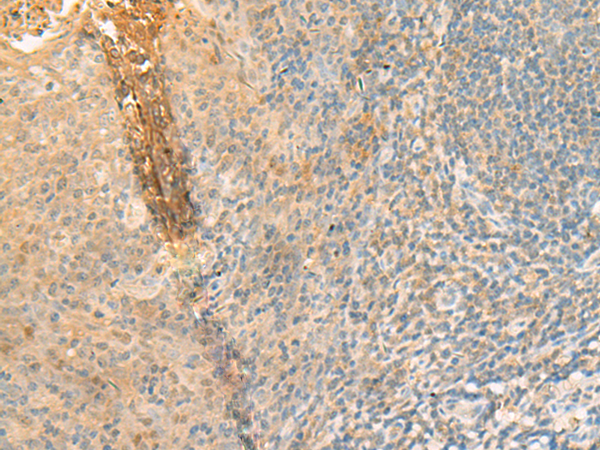

分类: 科研抗体货号: P13515别名: GPCR1; GPCR150应用: IHC反应种属: Human